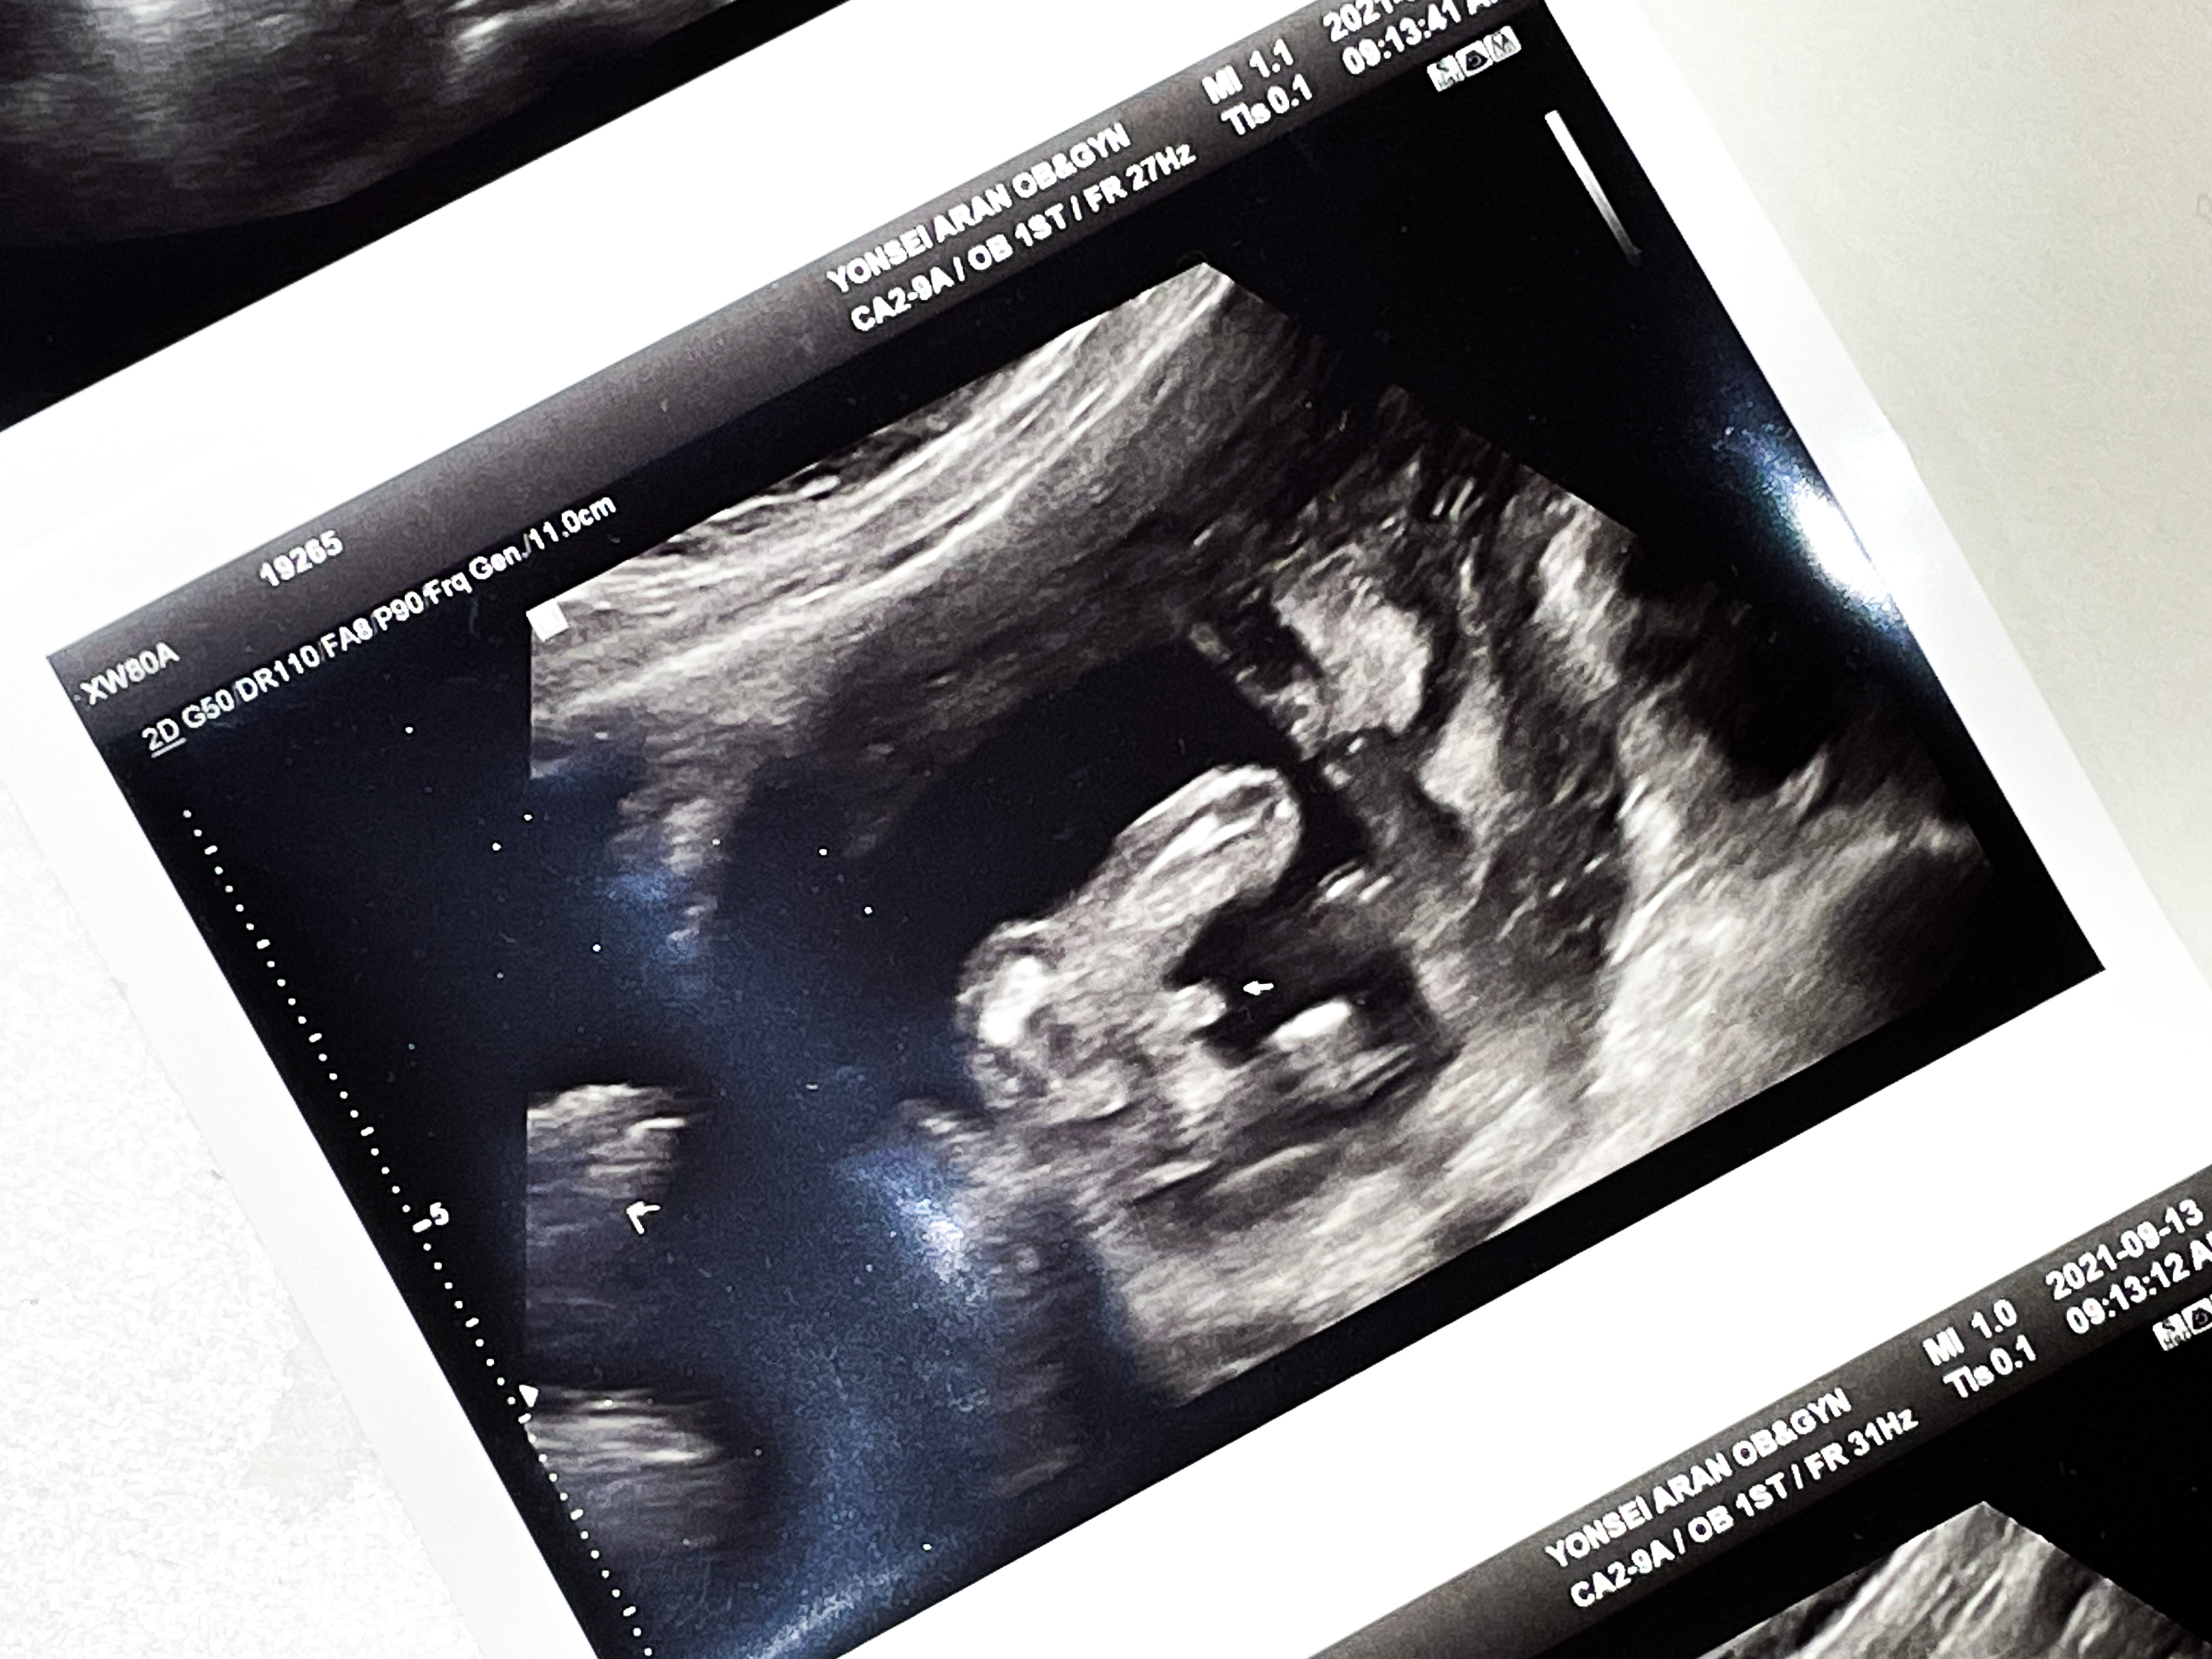

15주 4일 2차 기형아 검사를 받으러 갔다.

먼저 담당 원장님과 초음파를 확인했다.

벌써 애가 많이 커서 한 프레임 안에 담기지가 않았다.

애기가 한프레임 안에 안담기다보니 앉은키를 잴 수 없다고 했다.

대신 정강이뼈 길이, 몸무게 등등을 측정해주셨다.

체중(EFW): 132g

머리직경(BPD): 3.26 cm

머리둘레(HD): 12.35 cm

복부둘레(AC): 10.68 cm

허벅지길이(FL): 1.57 cm